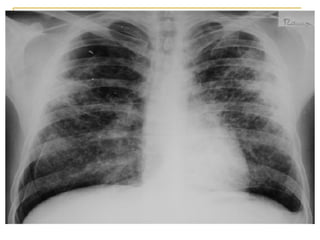

Radiografía de tórax obtenida al ingreso (compromiso intersticial   )

Radiografía de tórax control a los 5 días del ingreso (opacidades tipo “vidrio esmerilado” )